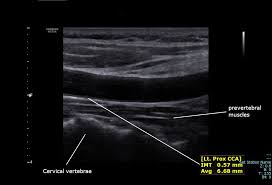

경동맥 초음파 검사는 고주파 초음파를 사용하여 목의 경동맥 혈관을 영상으로 확인하는 검사입니다. 혈관 내벽 두께, 혈류 흐름, 좁아진 정도 등을 실시간으로 볼 수 있으며, 조영제나 방사선 노출이 없어 안전합니다. 검사 시간은 약 20~30분 정도 소요됩니다.

환자는 검사 침대에 누운 후, 목에 젤을 바르고 초음파 탐촉자를 대어 경동맥을 관찰합니다.

혈관 내막 두께, 협착 정도, 혈류 속도 등을 확인할 수 있으며, 결과에 따라 추가 정밀검사가 필요할 수 있습니다.